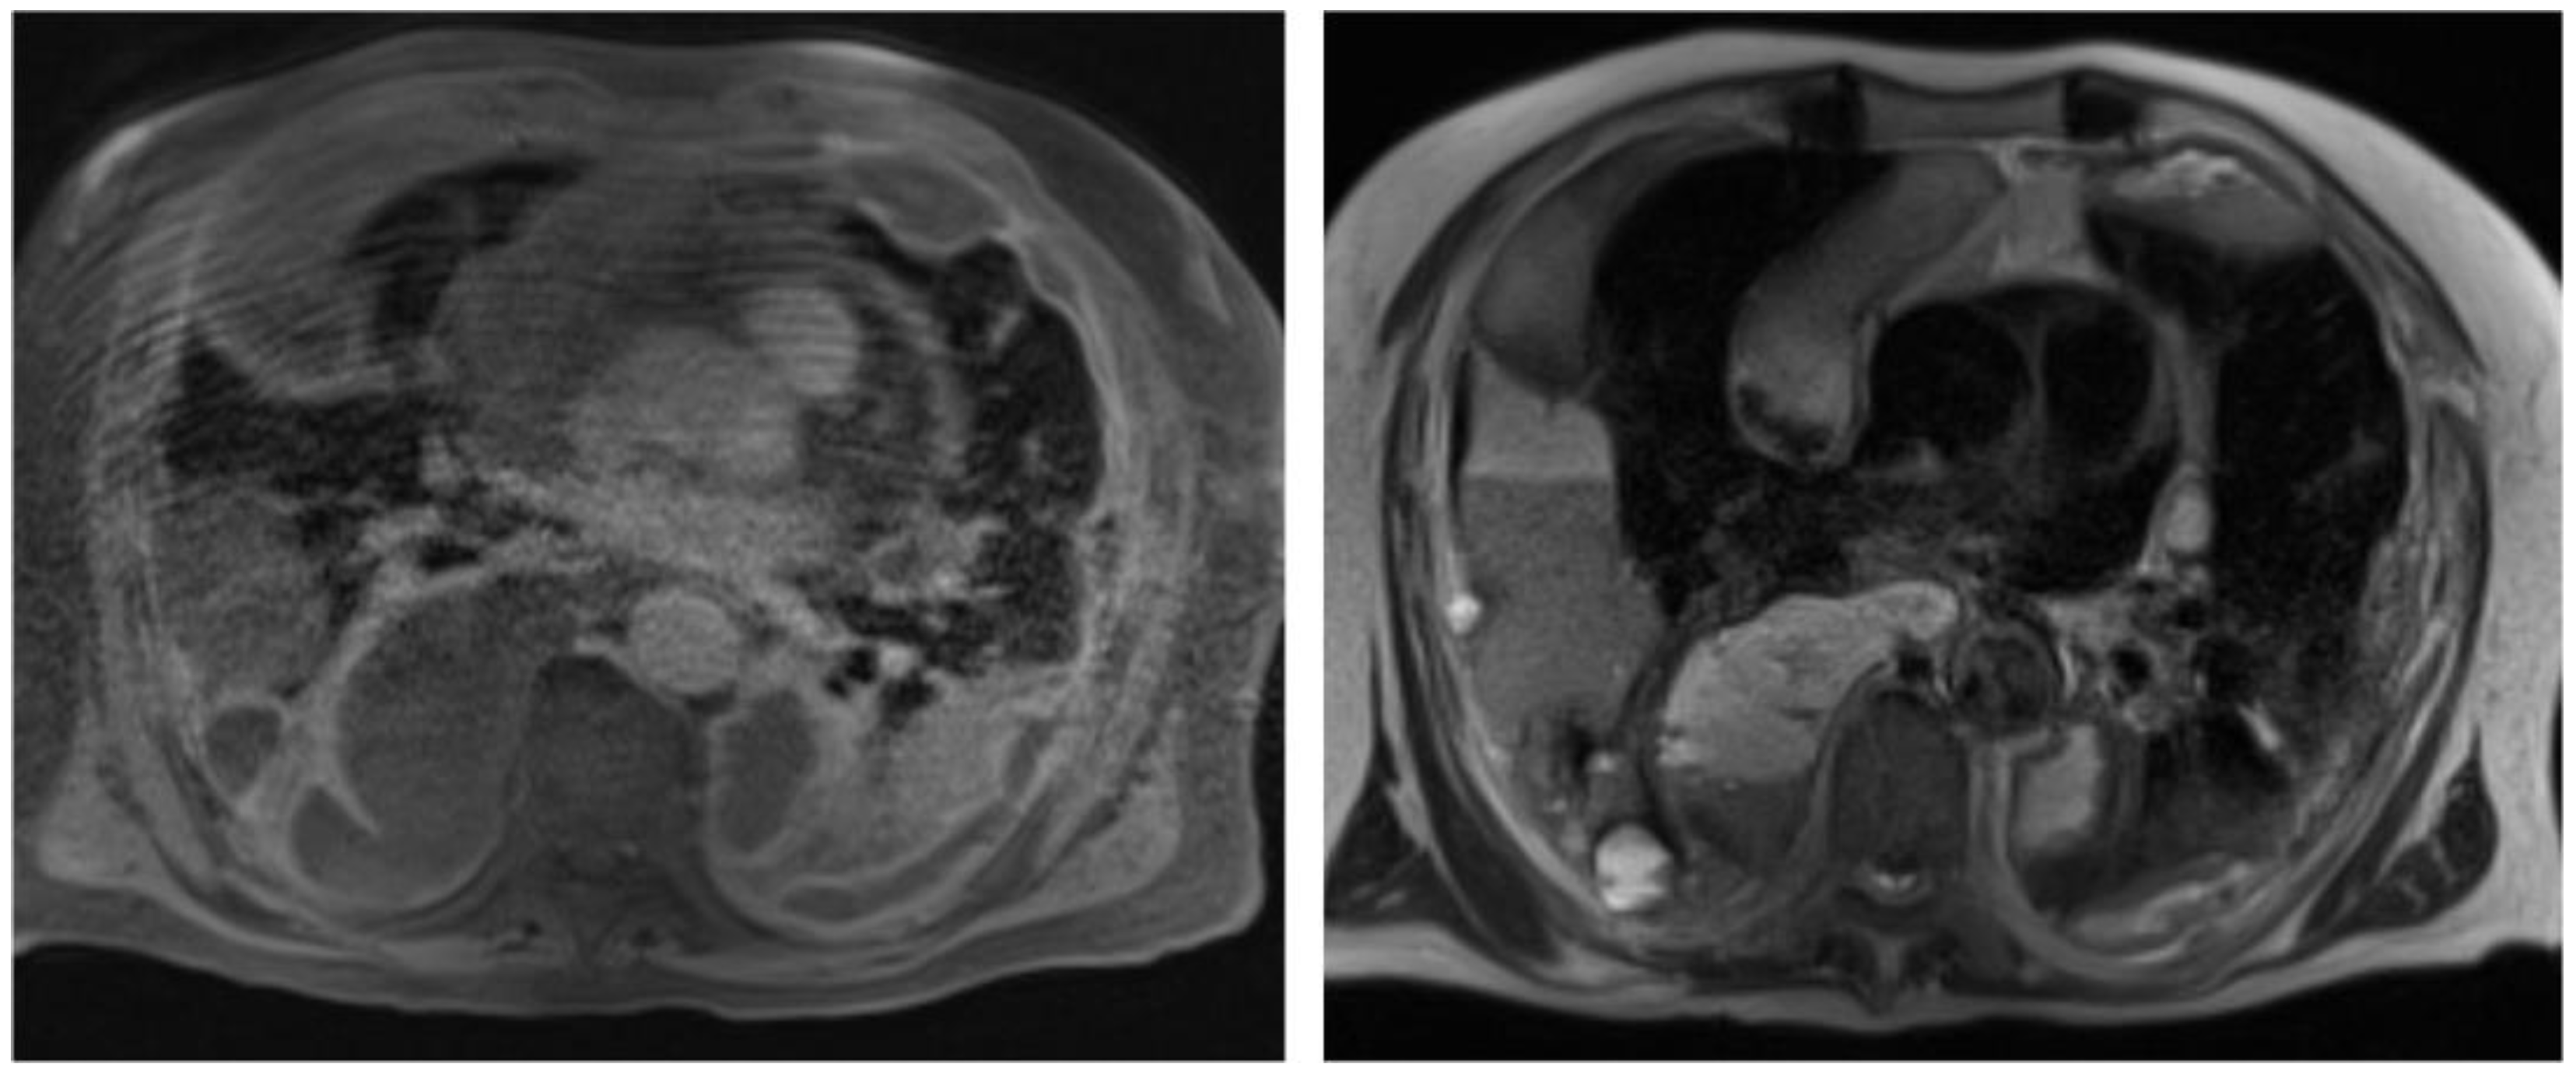

2. Case Report